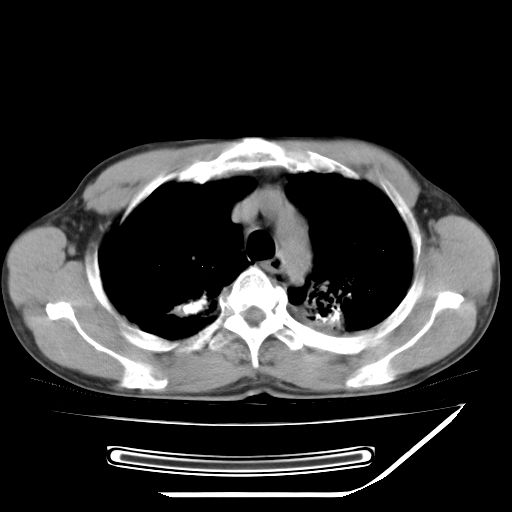

男,59岁,“结核性胸膜炎”30余年,胸部经常疼痛,多次x检查提示“肺部”炎症。腹部疼痛5日,b超提示:“肝内短管结石,余显示不清,建议进一步检查。”

两肺结核并右侧胸腔积液;脾脏、腹腔及腹膜后淋巴结结核[陈旧性];肝内胆管结石

胸部腹部都是结核(双肺。纵隔淋巴结,肝脏,脾脏,肠系膜)